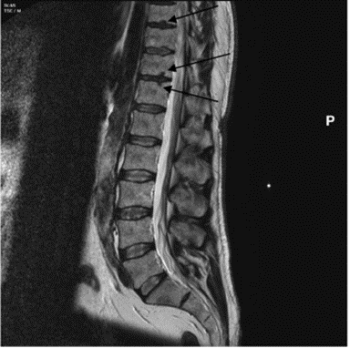

Schmorl’s nodes are depressions on the superior and/or inferior surfaces of the vertebral body (figure 1), due to herniation of the nucleus pulpous through the cartilaginous end plate. They are most common on the lower thoracic (T8-T12) and the upper lumbar vertebrae (L1-L2) (Rogers and Waldron 1995, 27). Schmorl’s nodes are of significant interest in bioarchaeology and have been used to interpret past human health and lifestyle and offer an indication of trauma within a historical population (Üstündağ et al. 2010; Novak et al. 2012). Clinically they are frequently asymptomatic but can cause acute backpain, and thus present a problem in modern populations (Kyere et al. 2012, 2119; Abu-Ghanem et al. 2013). The reported clinical and palaeopathological literature indicates that Schmorl’s nodes prevalence ranges vastly between 5 and 70% (Silberstein et al. 1999, Dar et al. 2010, 672). Comparison between historical populations is difficult due to variation in the methodological approach of assessing Schmorl’s nodes, in addition to a limited understanding of the aetiology of the condition (Matt and Rehman et al. 2014; Trzciński et al. 2017, 301-303). Clinically, magnetic resonance imaging (MRI) (figure 2) is used to assess the number and severity of Schmorl’s nodes in living individuals (Mattei and Rehman 2014, 39). In osteoarchaeology, the pathology is often identified and assessed during post-excavation analysis of past populations via macroscopic techniques.